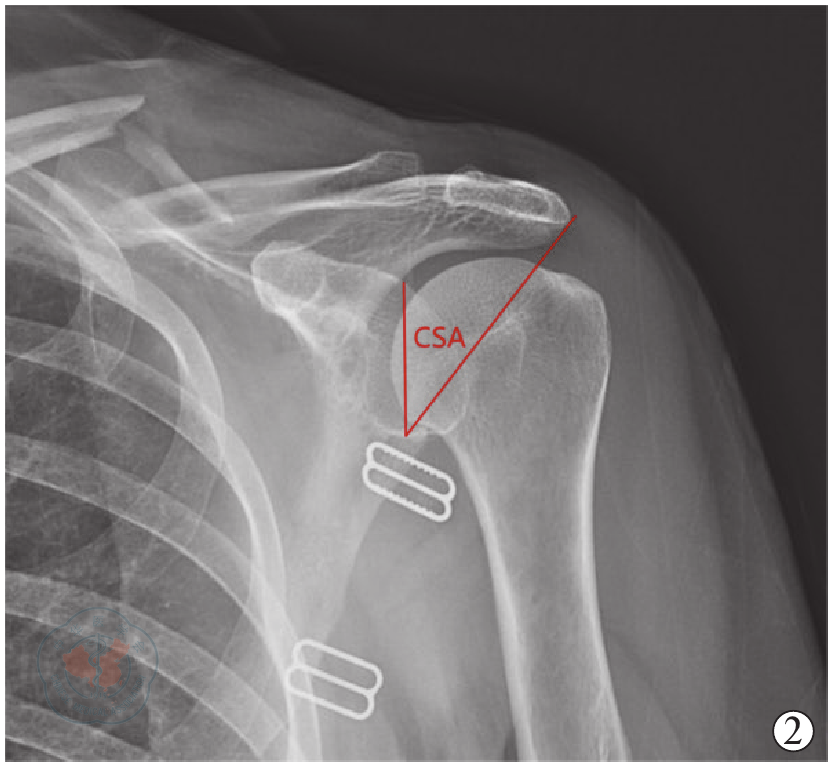

图2 对照组CSA(肩关键角)测量方法示意图

Figure 2 Schematic diagram of the measurement method for CSA in the control group